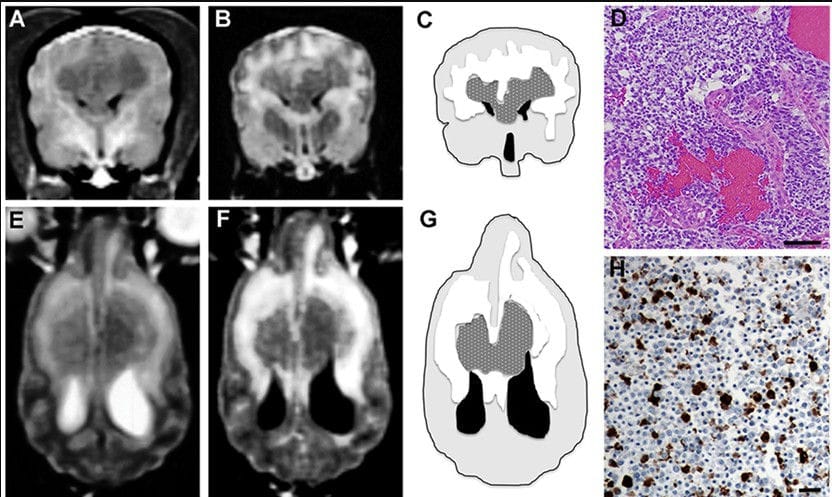

Symmetrical butterfly glioblastoma, Case 3. Transverse T1 (A) and FLAIR (B) MR images at the level of the cruciate gyrus, demonstrating an intra-axial, bilaterally symmetric mass lesion present in the frontoparietal regions. Schematic, MR intensity-segmented transverse (C) and dorsal planar (G) representations of symmetrical bihemispheric appearance of butterfly GBM (stippled gray), perilesional edema (white), brain parenchyma (light gray), and ventricles (black). Histopathological features of GBM (D) include marked hypercellularity, cellular pleomorphism, and microvascular proliferation. Oligodendroglial components of the tumor are present throughout the section (H&E stain, bar = 200 μm). In the dorsal planar PD-T2 (E) and FLAIR (F) images, the mass attenuates the rostral aspects of the lateral ventricles and is associated with extensive symmetrical perilesional hyperintensity within the surrounding white matter, consistent with edema. The mass demonstrates heterogeneous signal intensity in all sequences. (H) 50% of neoplastic astrocytes demonstrate intense GFAP staining, while neoplastic oligodendrocytes lack GFAP immunoreactivity (GFAP stain, horseradish peroxidase with 3,3′-diaminobenzidine substrate, bar = 50 μm).